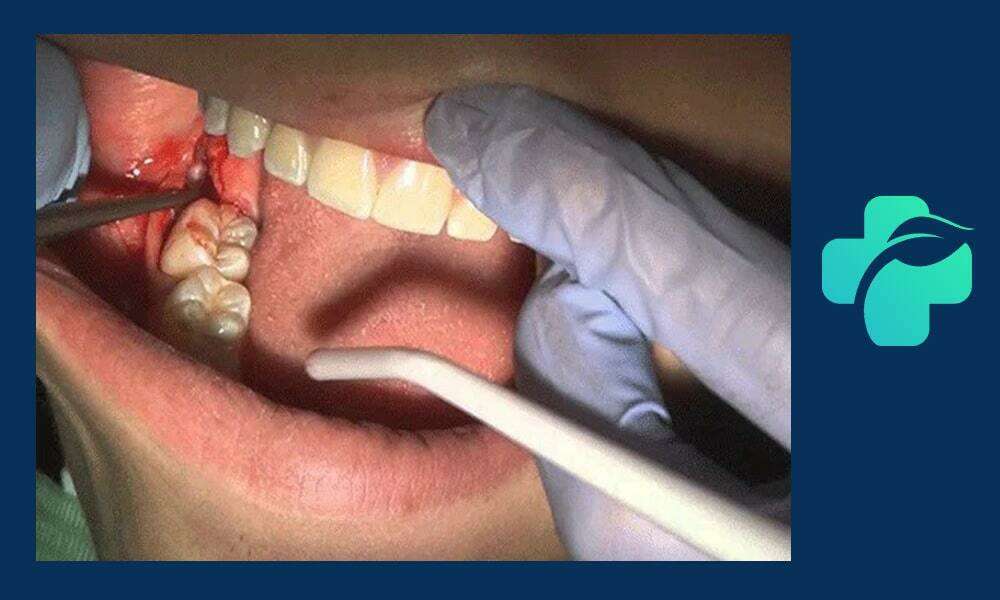

مراحل جراحی دندان عقل نهفته

فرایند جراحی دندان عقل نهفته اغلب شامل مراحل زیر است:

- بی حسی موضعی یا بیهوشی: بسته به پیچیدگی جراحی، پزشک نوع بی حسی را تعیین می کند.

- برش لثه: ایمپلنت برش خورده و دندان یا استخوان اطراف آن آزاد می شود.

- برداشت دندان عقل: دندان به صورت بخش بخش برداشت می شود تا آسیبی به بافت های اطراف وارد نشود.

- دوخت لثه: برش لثه با بخیه بسته می شود تا زخم سریع تر التیام یابد.